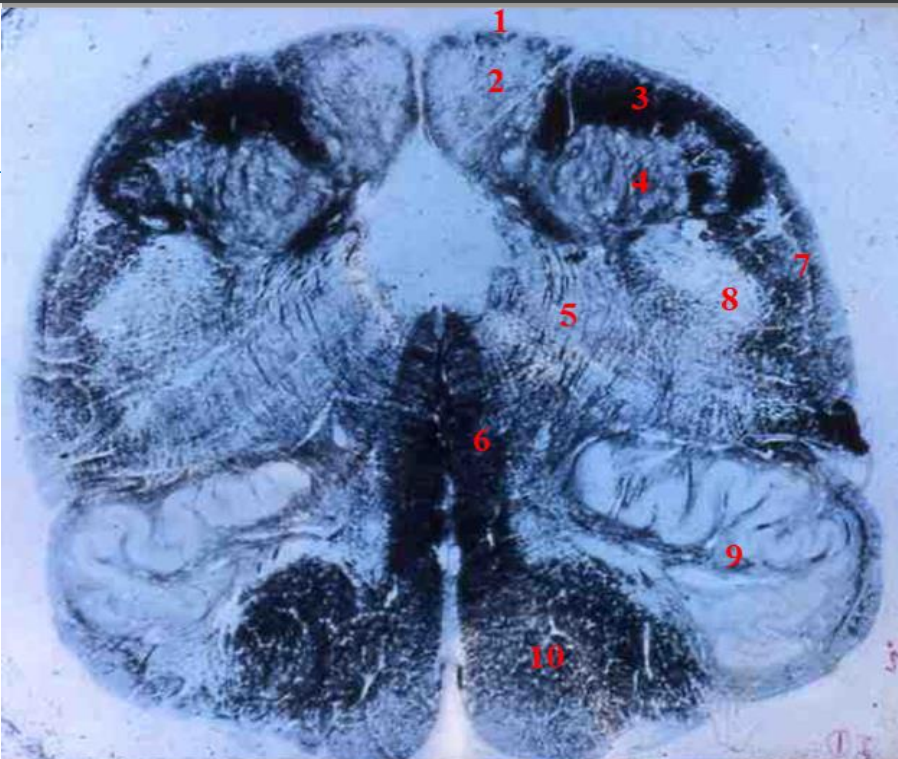

Q

indentify the weigert

A

cervical cord

- fibre tracts are larger

- grey matter is large

- brachial plexus

- no lateral horn

12

1

fasiculus gracilis

13

2

fasciculus cuneatus

14

3

posterior horn

15

4

anterior horn